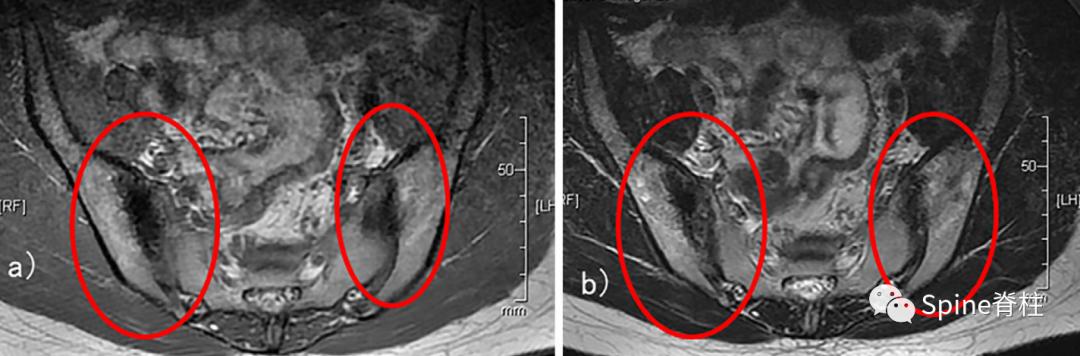

上述同一个病例,MRI也提示骶髂关节髂骨侧硬化 (下图)。